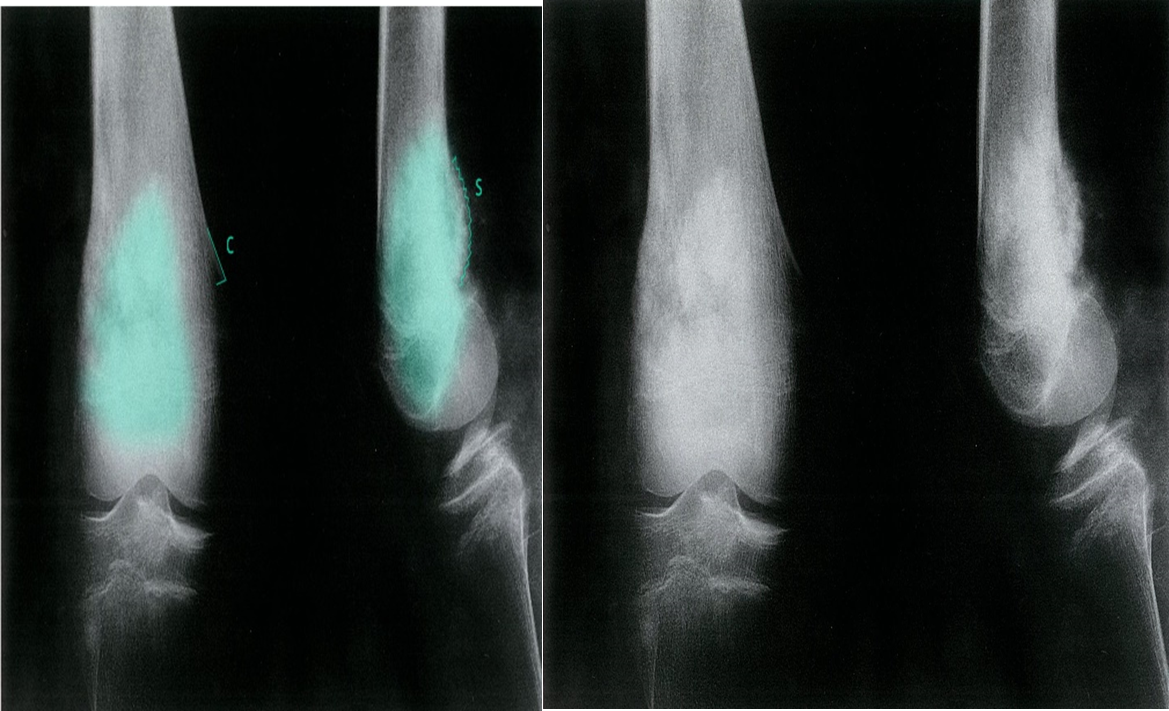

Osteosarcoma of the distal femur

- X-ray right knee (AP and lateral views) of a patient with osteosarcoma

- An ill-defined cloud-like lesion with a wide zone of transition (green overlay) is seen in the distal femur. An aggressive type of periosteal reaction known as a Codman triangle (C) is visible medially. Additional aggressive periosteal reaction seen posteriorly has produced a sunburst pattern (S).